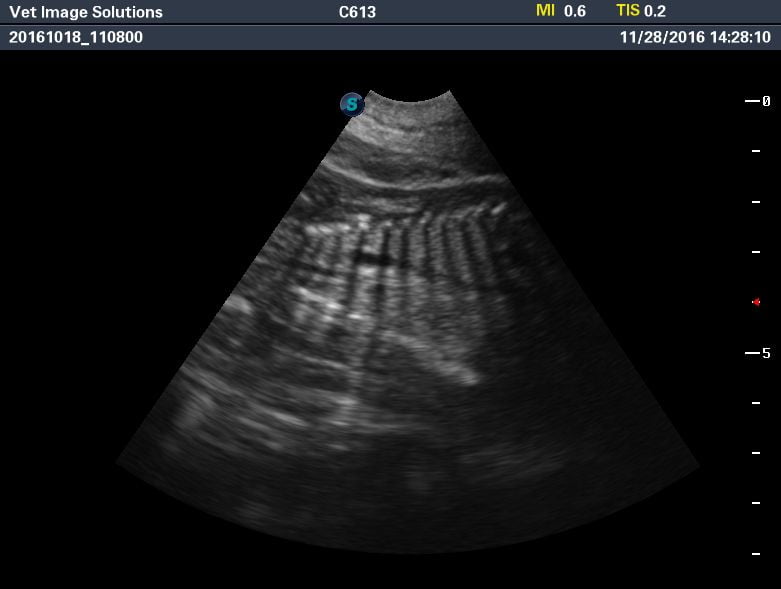

Towards the end of the video, we see a puppy and its limbs in cross section.